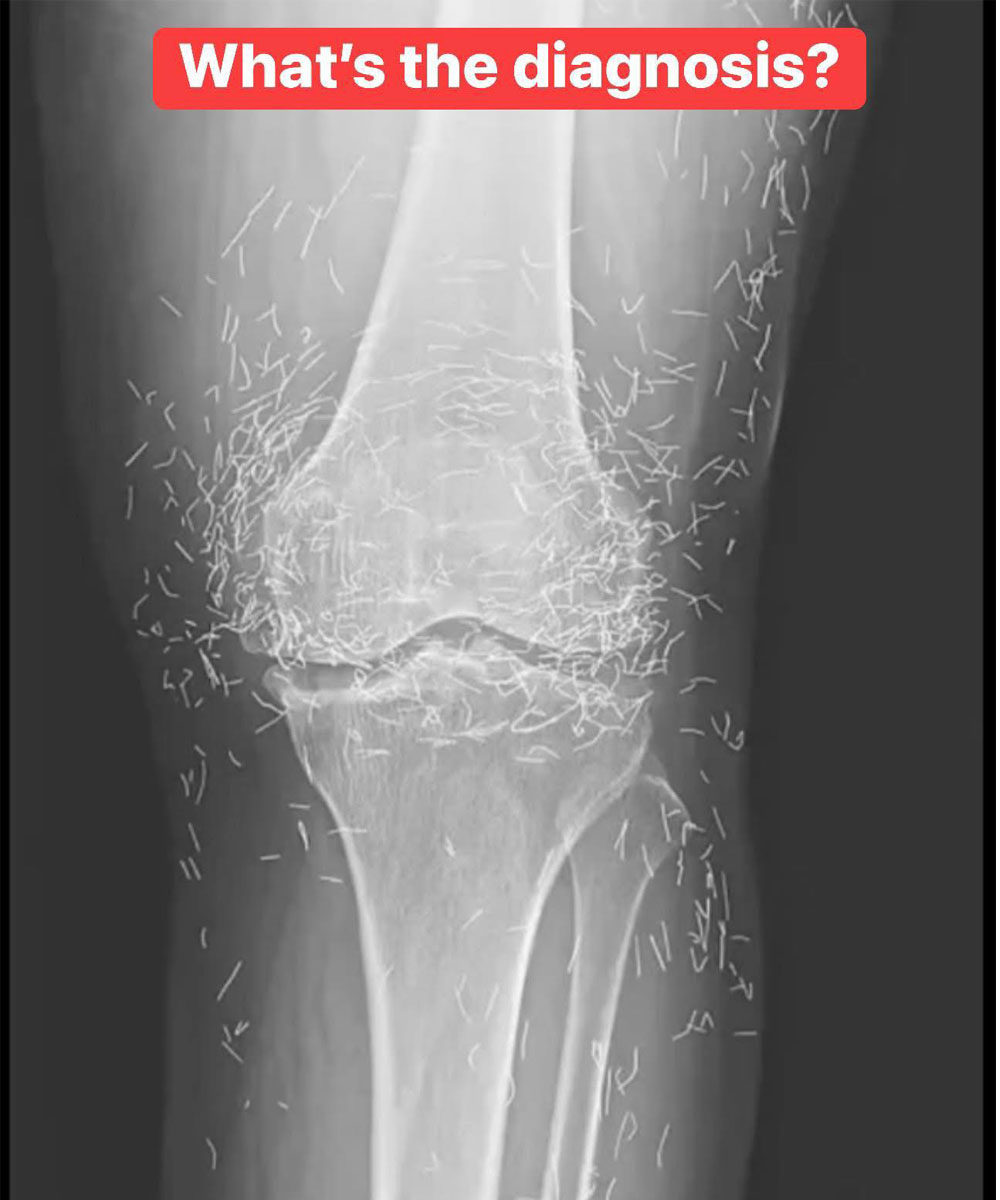

X-Ray Reveals Hundreds of Gold Needles in Woman’s Knees

As doctors examined an X-ray image of the knees of an old woman experiencing severe joint pain, they found a gold mine: hundreds of tiny gold acupuncture needles left in her tissue.

The 65-year-old woman from South Korea had previously been diagnosed with osteoarthritis, a condition in which the cartilage and bones within the joints degrade, causing pain and stiffness. However, when pain relievers and anti-inflammatory drugs didn’t alleviate the pain in her knees and only caused stomach discomfort, she had turned to acupuncture, the doctors wrote last week in the New England Journal of Medicine.

Acupuncture is an alternative medical practice that uses needles in order to purportedly stimulate certain points on the body, to alleviate pain or to treat a variety of diseases.